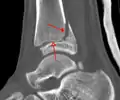

A triplane fracture of the ankle as seen on CT

- Triplane fractures are a special type of fracture that involves the immature skeleton. It has a coronal plane in the metaphysis, an axial plane in the physis and a sagittal plane in the epiphysis.[14]